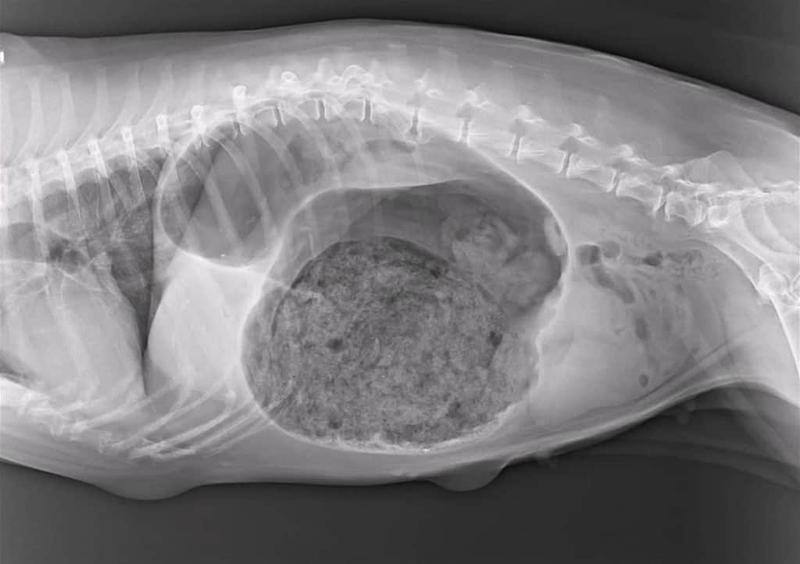

Niemniej jednak, twardy brzuszek u psa nie zawsze jest wynikiem diety czy pośpiechu przy jedzeniu. Należy pamiętać, że problemy zdrowotne, takie jak zapalenie trzustki, niedrożność jelit czy nowotwory, mogą również powodować tę uciążliwą dolegliwość. Kiedy pies nagle staje się apatyczny, ma twardy brzuch, wymiotuje lub unika jedzenia, koniecznie powinien jak najszybciej trafić do weterynarza. Bez względu na to, czy problemy są błahe, czy poważne – lepiej dmuchać na zimne!